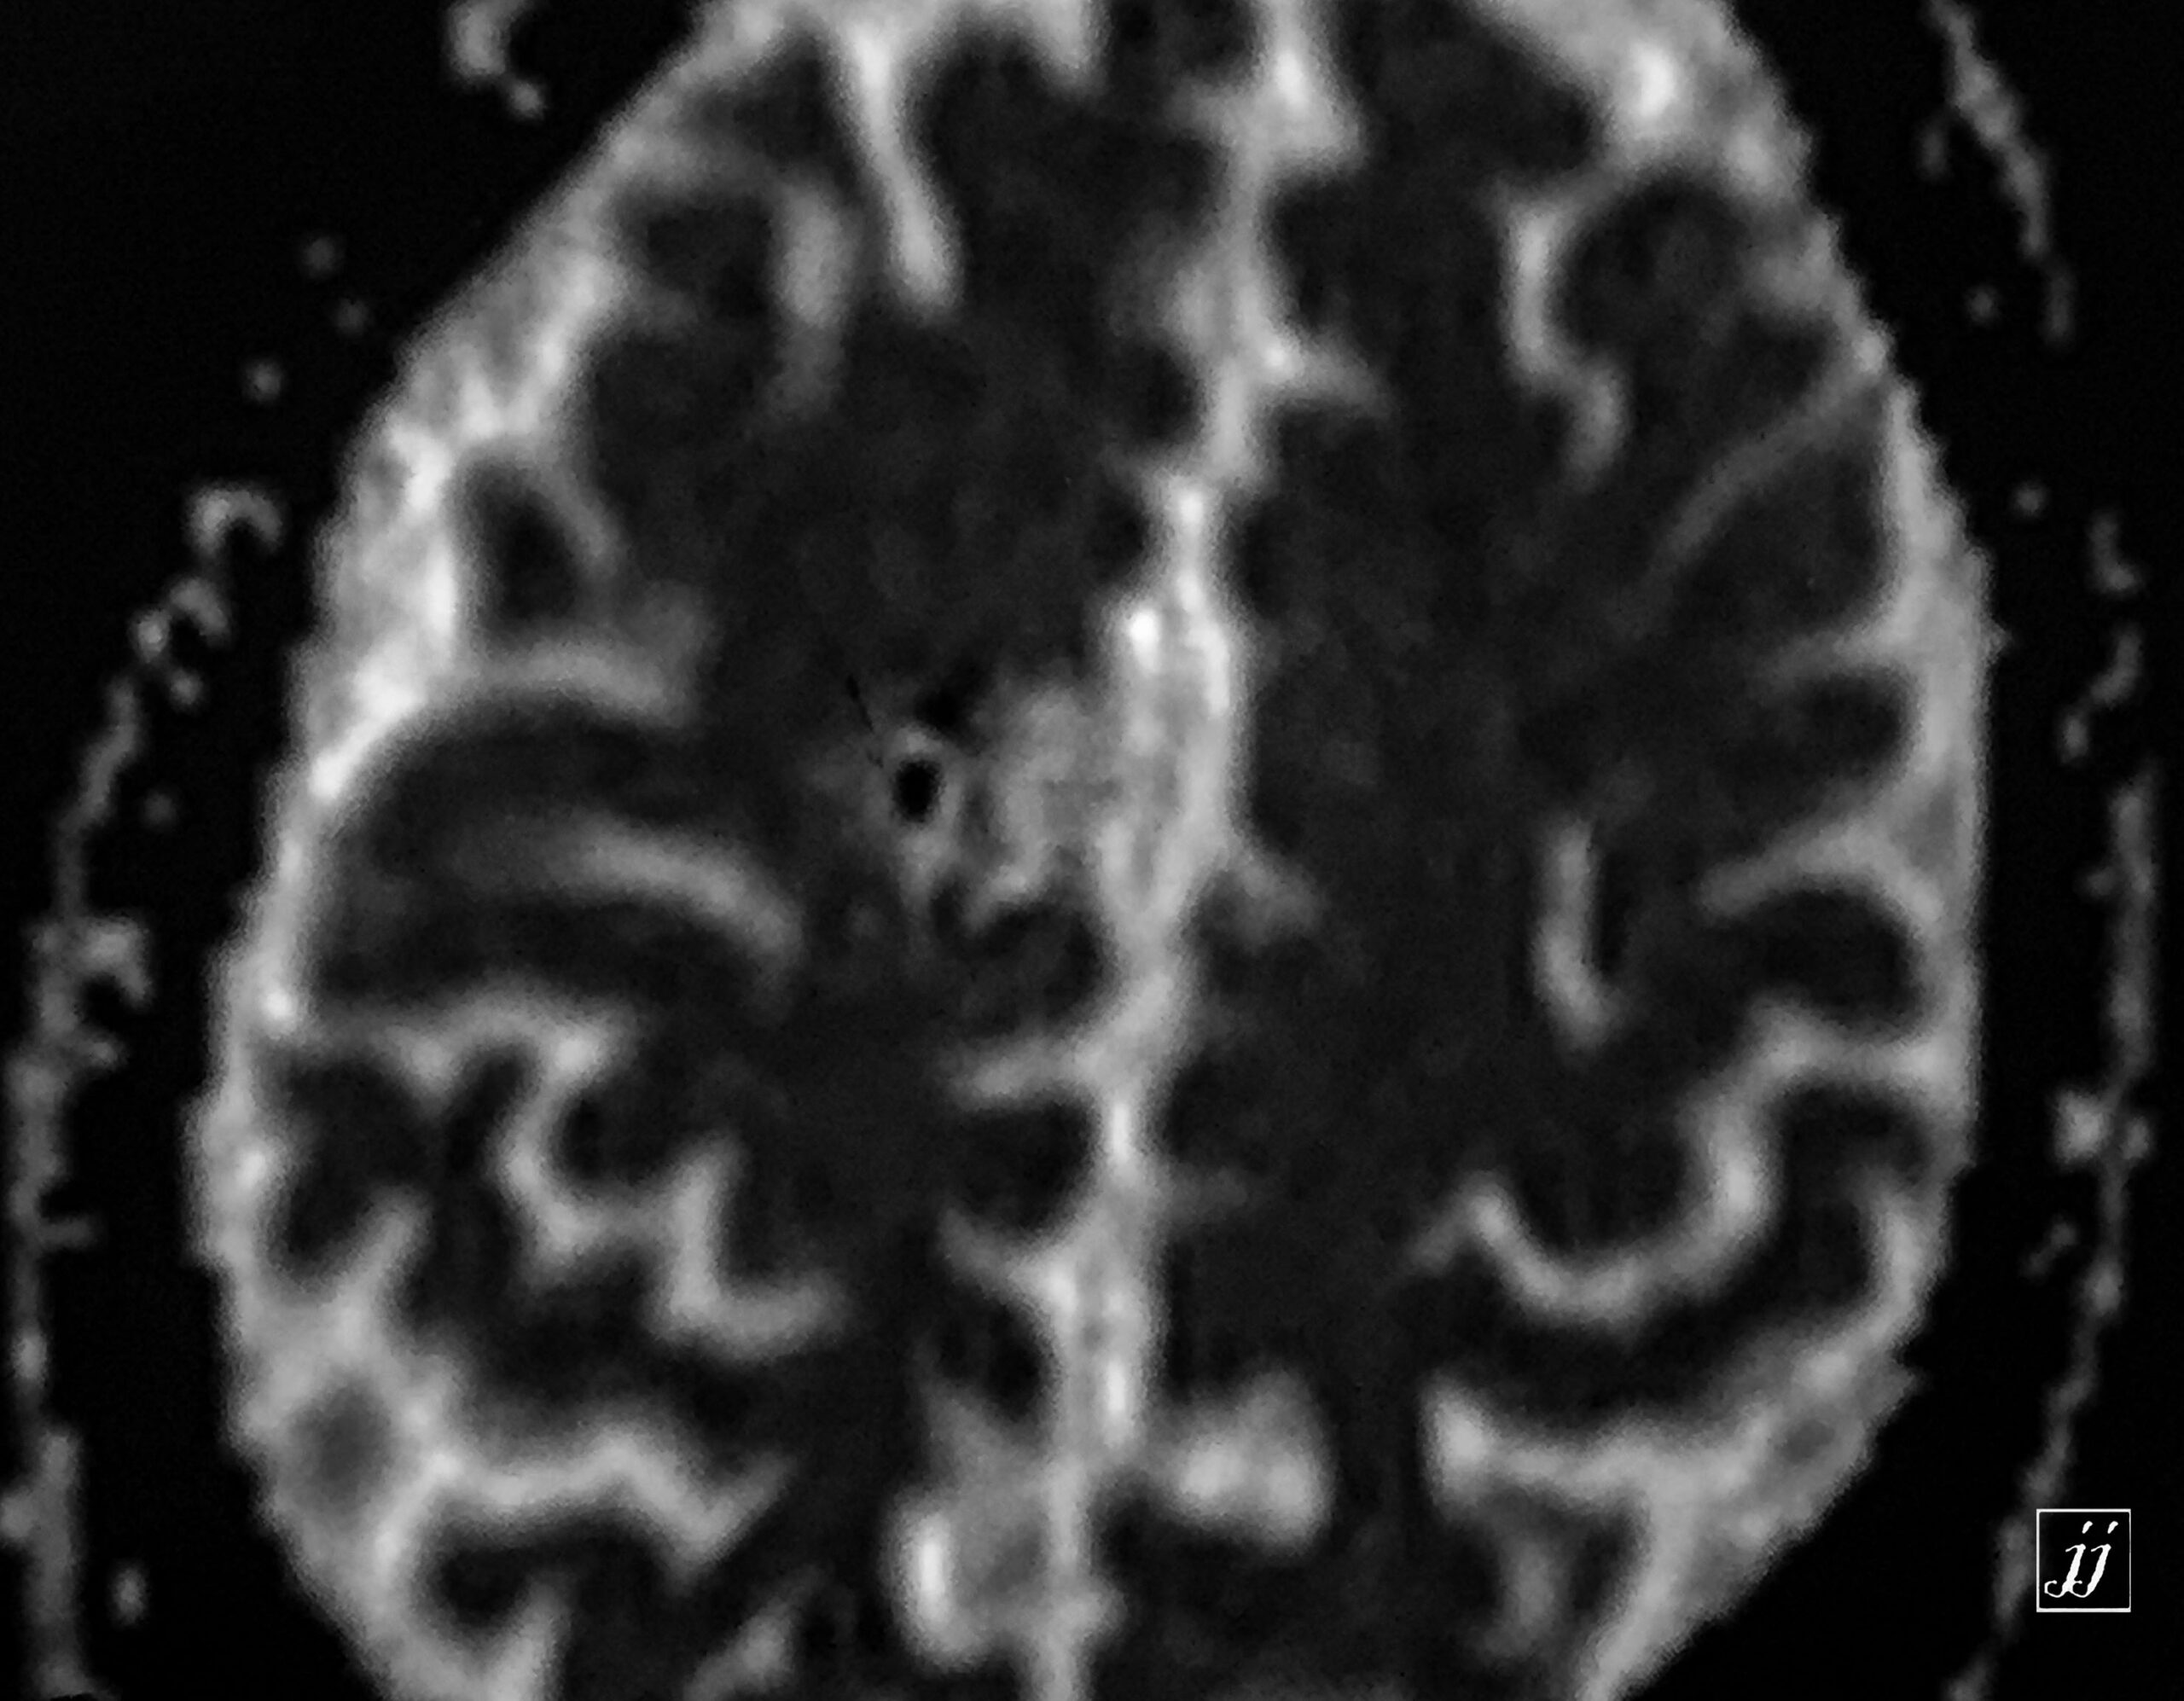

Brain- cavernoma (6)